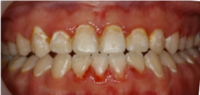

Foto på white spot lesions och karies

En bieffekt av ortodontibehandling är white spot lesions och karies.

Foto på karies i framtänderna

Karies i framtänderna på patient som haft tandställning.